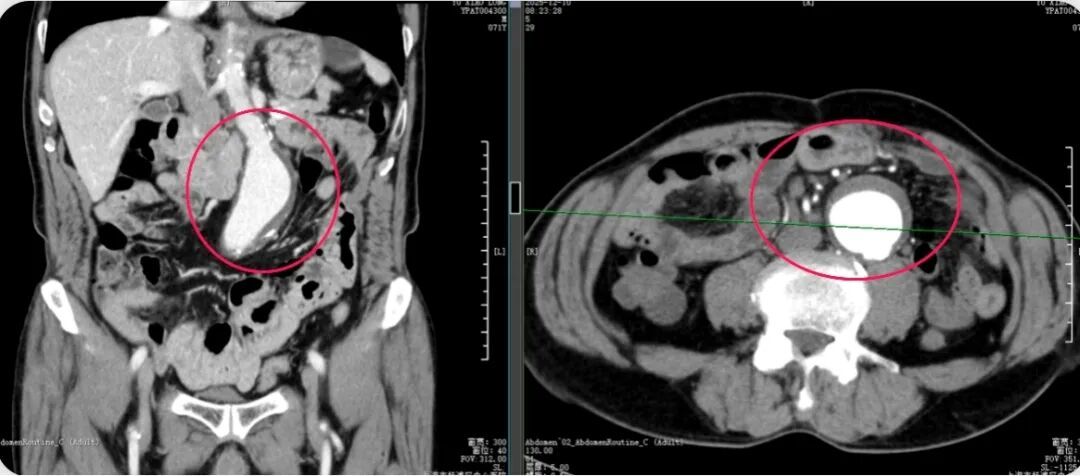

因便血入院时,老张并未意识到问题的严重性。然而,胃镜、肠镜、增强CT……一系列检查后,诊断结果如晴天霹雳:直肠中段腺癌;更令人倒吸一口凉气的是,检查竟意外发现老张的腹主动脉存在孤立性夹层,且直径已超过5厘米。

主动脉夹层

“这在医学上极其凶险。”主治医师李清华打了个形象的比喻:“把主动脉想象成一根三层结构的水管。正常情况下三层紧密贴合,一旦内层破裂,血液就会像洪水一样钻进夹层,像轮胎鼓包一样越撑越大。老张的血管‘鼓包’已达5厘米,随时可能‘爆胎’,一旦破裂,患者可能在几分钟内因大出血死亡。”

第一战,拆除“血管炸弹”。血管外科团队采用了EVAR(血管腔内修复)技术在老张的双侧大腿根部切开各一个约1厘米的小口,通过导管将覆膜支架精准置入主动脉病变部位。支架如同一层坚固的“补丁”,迅速将血液与破损的血管内壁隔绝,“炸弹”被成功拆除。全程无需开腹,出血少,血压平稳过渡。